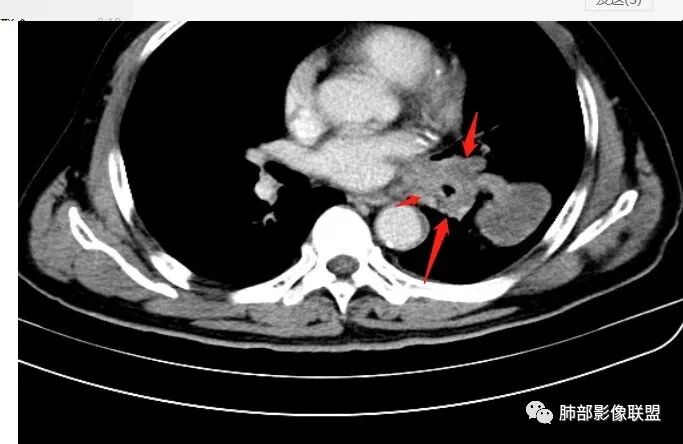

恶性没问题吧  ,哪位老师标示一下病灶

那些是淋巴结?哪是主病灶?

支气管如何?肺动脉?肺静脉?

南边:我发一个图

南边:这病灶与支气管啥关系啊?

南边:与肺静脉啥关系?这样追下去是不是很恶啊

尘缘:@南边 肺静脉受侵

南边:病灶分为两大块,外围囊实性大肿块,支气管关系不密切,内带多发淋巴结,侵犯支气管、肺血管,恶性没问题,按理间叶为主,或不典型的癌,这不是一个中央型的肺癌,是外朝内进展的,奇怪的是边界这么清楚光滑,一般癌肉瘤、肉瘤类多,其次才是癌,远端也没有阻塞,大方向是这样,恶性,间叶来源?或者混合,恶性程度较高,鉴别就是结核,因为结核是妖

1.左肺下叶近肺门区肿块,肿块外围大,内带小,提示外围向中央生长,符合周围型SCLC沿支气管方向生长。

4.病灶区支气管以受压推移为主,管腔不规则,腔内通而不畅,提示病灶粘膜下为主,符合SCLC迁徙蔓延或间叶来源肿瘤。

5.病灶内有血管走行,血管局部受压,但是强化考虑为乏血供,提示病灶内肺动脉并不是供血血管,只是病灶侵袭性强把血管包埋而已,为血管包埋征;血流面光滑,血管包埋符合SCLC。

6.左肺门淋巴结肿大,与病灶局部融合分界不清,呈冰冻肺门;而纵隔内未见肿大淋巴结,冰冻肺门符合SCLC,但是病灶主体那么大,纵隔内没有明显肿大淋巴结,不是很符合SCLC娘小崽大的特点。